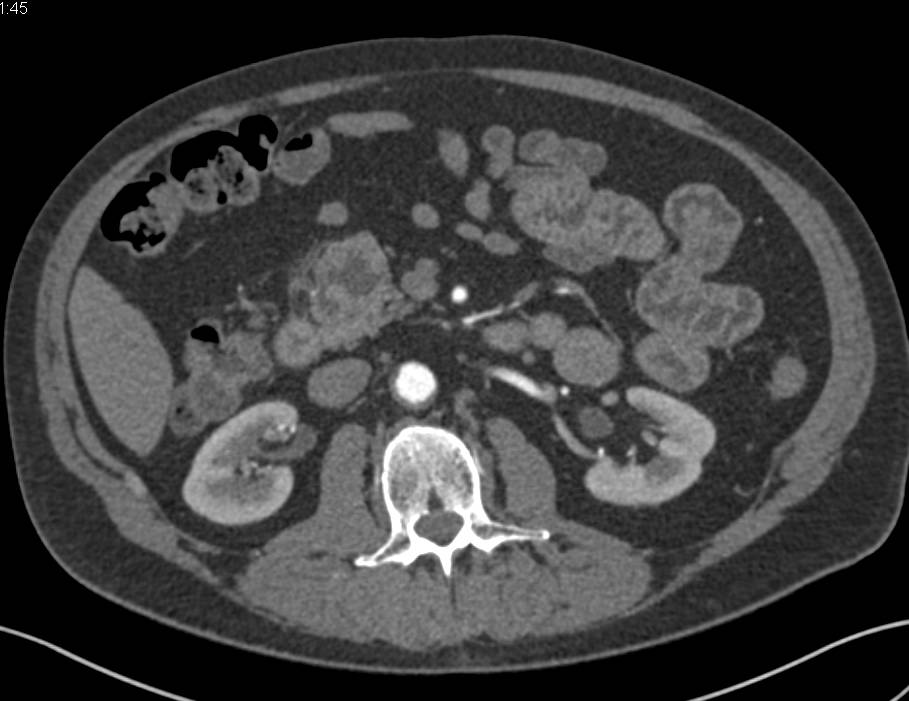

Renal Cell Carcinoma Metastatic to Pancreas, Bone and Stomach